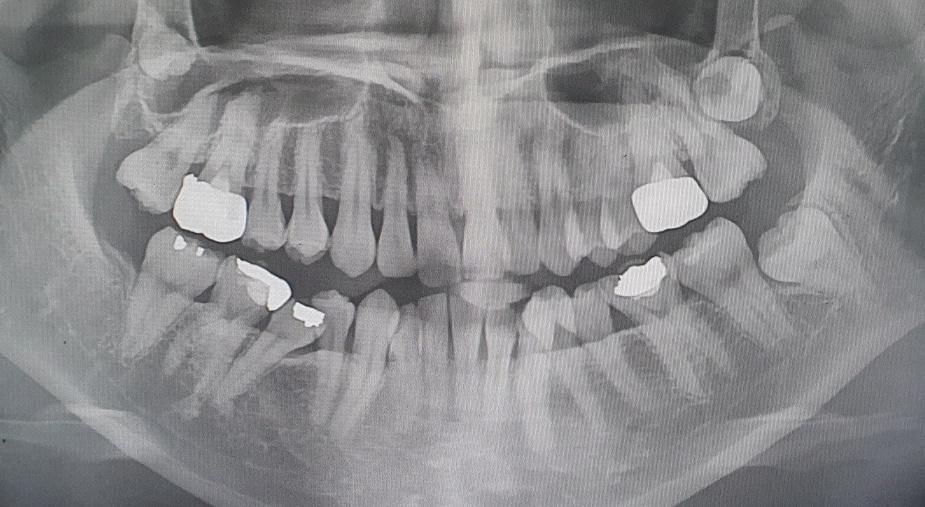

사랑니가 3개가 있는데 어떻게 해야할까요?

사랑니.. 치과쌤께서 안올라 올거라고 하셨었는데 시간 지나니 올라오네요ㅠㅠ위에 두개는 위치도 안좋고 누운거같은데 발치가 되나요?

위에 2개 사랑니는 내려올 가망 없습니다 발치 원한다면 대학병원 구강 외과 가보시기 바랍니다

사랑니가 매복되어 있고 별다른 문제를 발생시키지 않는다면 굳이 발치를 할 필요는 없습니다.

사랑니가 매복된 상태라 특별한 이유가 없다면 발치를 안하셔도문제가되진 않을것같습니다.